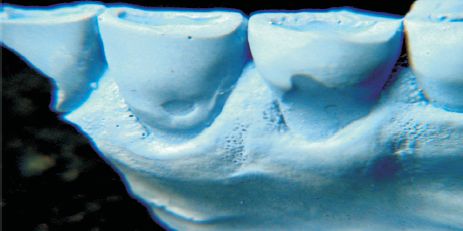

Fig. 26, 27, 28 y 29. Investigación realizada con material esqueletario del Museo Nacional de Antropología proveniente de la zona conocida como "Cerritos de Rocha" (Uruguay). Comprende a individuos maduros que presentan reabsorción ósea y aumento de corona clínica. Se observa gran abrasión por masticación primitiva y atricción con contactos fuera de áreas no funcionales, (¿Bruxismo, Thegosis?). Fuerzas friccionales importantes que desarrollaron una fuerte musculatura y sólita arquitectura ósea. Balanceo bilateral. El individuo de la fig 29 presenta un marcado y asimétrico desgaste incisivo compatible con la utilización de la dentadura como herramienta. No hay presencia del LCNC.